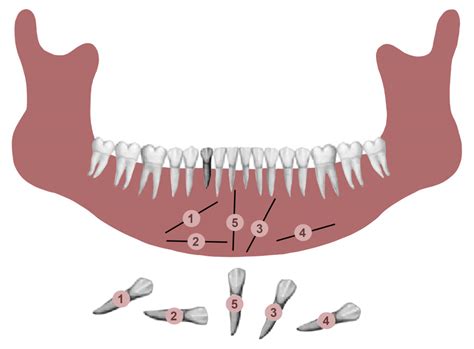

An impacted canine tooth occurs when the tooth is prevented from erupting into its proper position in the dental arch. This often happens because the tooth is blocked by other teeth, the jawbone is too small, or there is an abnormal growth path. The maxillary (upper) canine is the second most common tooth to become impacted, following third molars (wisdom teeth). While it might seem like a minor inconvenience, leaving an impacted tooth untreated can lead to serious complications, including the absorption of the roots of neighboring teeth or the development of cysts.

Potential Complications of Untreated Impactions

Ignoring an impacted canine tooth is rarely advisable. The consequences of long-term impaction can be irreversible and may require more invasive procedures down the line. The pressure exerted by an impacted tooth can slowly erode the roots of the lateral incisors, potentially leading to the loss of those teeth as well. Furthermore, the follicle surrounding an impacted tooth can enlarge over time, turning into a dentigerous cyst. These cysts can destroy healthy jawbone tissue and necessitate significant surgical removal if left unchecked.